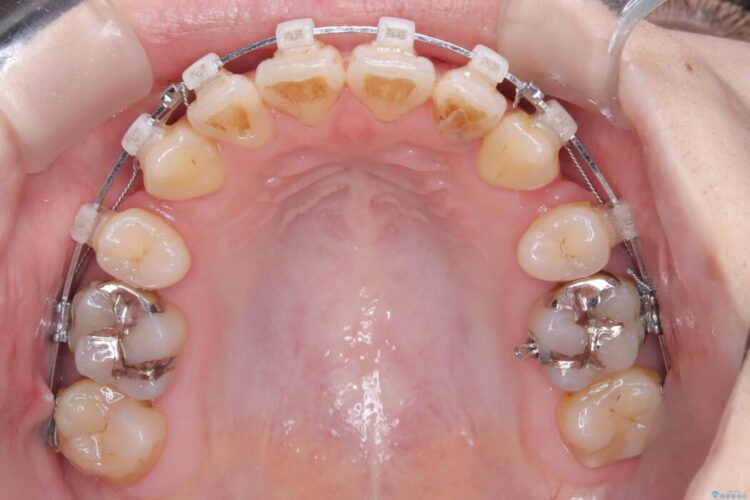

- 矯正装置:ワイヤー矯正(クリア装置)

精密検査の結果、上顎左右4番および下顎左右5番の計4本を抜歯し、目立ちにくいクリア装置にて治療を行いました。

気になっていたガタつきや開咬が改善され、見た目だけでなく咬み合わせの機能面も大きく向上し、大変ご満足いただけました。